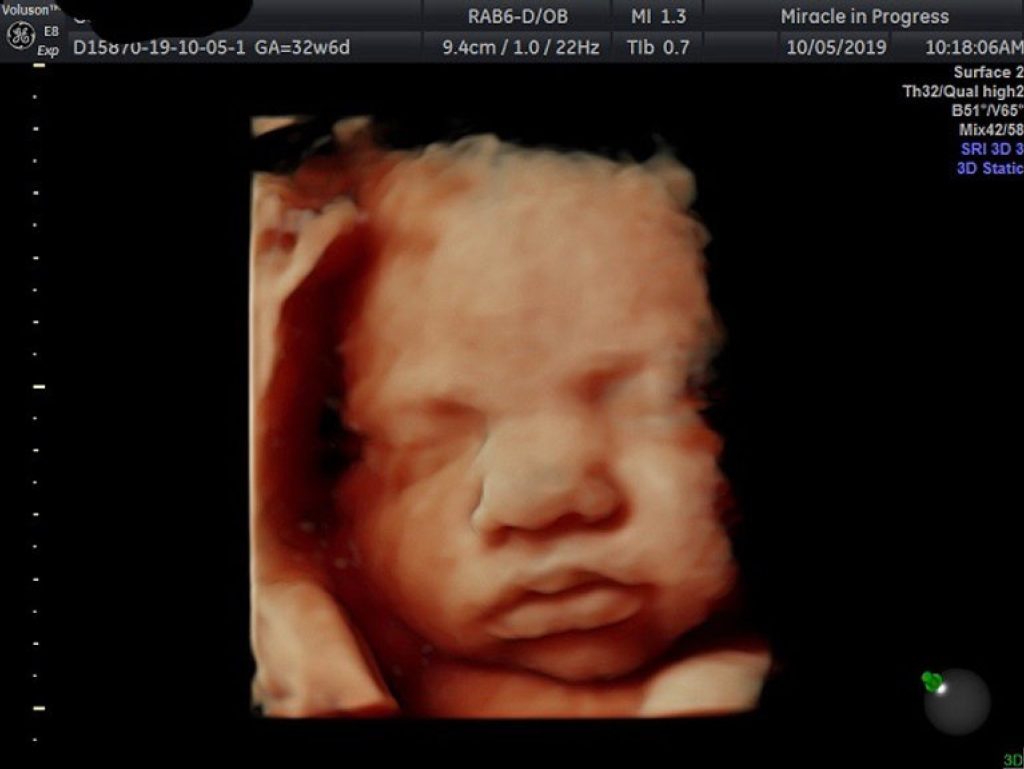

Ultrasound 3D memberikan gambar tiga dimensi yang lebih jelas.

Ultrasound 4D menambah elemen masa, memperlihatkan pergerakan janin secara langsung.

Ultrasound 5D pula menawarkan pengalaman yang lebih nyata dengan kualiti gambar yang lebih terperinci, membantu doktor dan ibu bapa melihat perkembangan janin dengan lebih jelas.